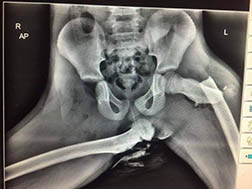

The X-ray, which, understandably, is careening around the internet today, shows the aftermath of a car crash in which a young woman in Wales was riding with feet up. One femur is snapped, while one hip is broken in the socket and the other has been dislocated far from where it should be.

Police who released the X-ray described the woman’s injuries as “life changing.”